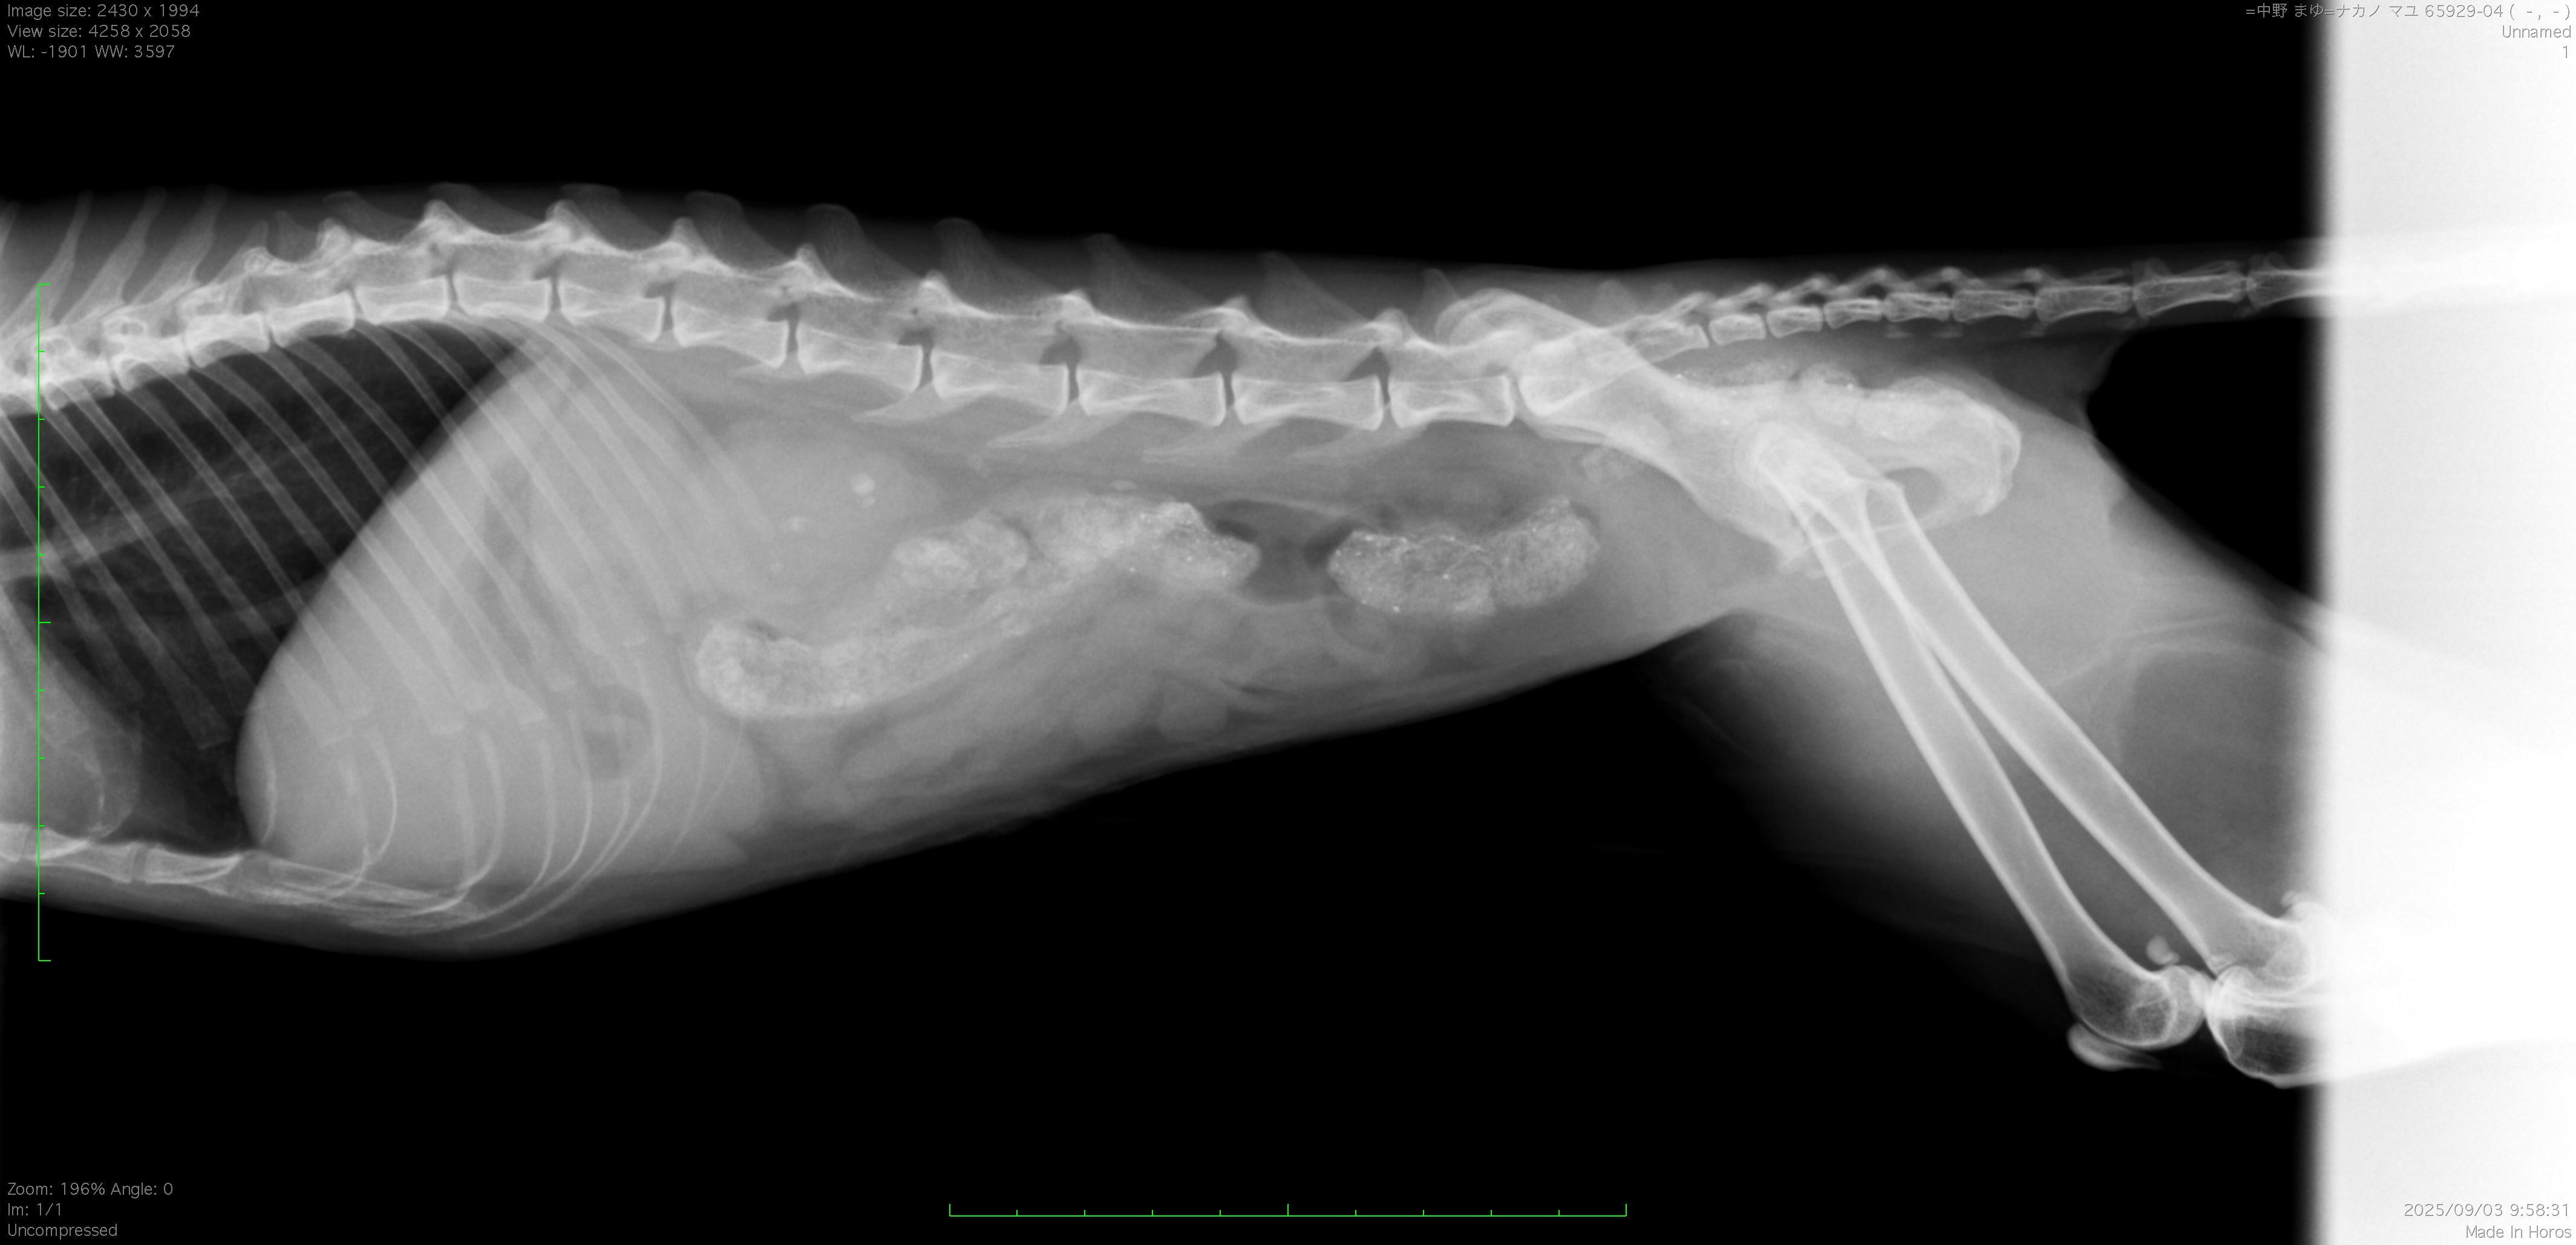

猫ちゃんが突然調子を崩し、元気食欲低下、嘔吐などの症状で来院。検査を実施したところ右の尿管に結石が閉塞しておりました。

尿管結石はX線で存在が特定でき、エコーにて詳しい位置を調べられます。しかしX線に写りにくい結石は見落としますし、エコーでは結石がないと診断するのが難しい場合があります(石が非常に小さい場合)。そこで当院では、その後の手術計画のためにも必要となるのですが、CT撮影を実施することで結石がどの位置にあるのか、一つだけなのか複数なのか、詰まった場所はどこのあたりか、などを特定し治療を実施していきます。

尿管結石は約2mm程度でしたが、そんなに小さな石であっても猫の細い尿管の内径(1mm程度の時もある)のため、閉塞するには十分な大きさです。結石の閉塞が認められ、CTでも尿が出ない状況が確認されたため、手術にて結石の摘出を実施しております。